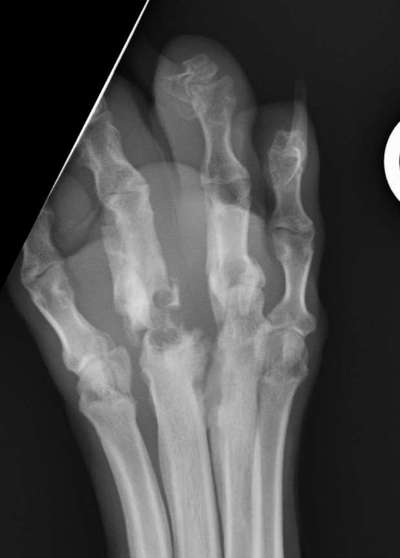

Es ist die rechte Hinterpfote und sie ist nach einer falsch behandelten Entzündung im Welpenalter deformiert, steif und hat riesige chronische Wunde die ständig infiziert sind. Durch die Deformierte Pfote kann er nicht richtig laufen. Leider kann das keiner mit einer Op beheben. Also bleibt nur der Weg Pfote ab

Die Zehengelenke wurden von den Bakterien zerstört, zerfressen und sind nun steif und verknöchert